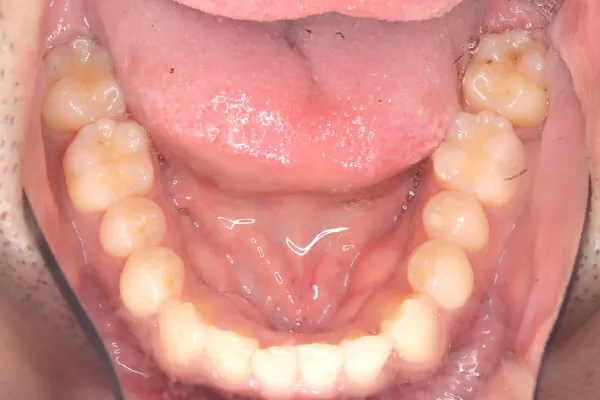

【30代男性】

下の歯のガタつきを

インビザライン矯正で

治療したケース

治療後

| 主訴 | 下の歯のガタつきが気になる |

|---|---|

| 期間 | 2年 |

| 費用 | 220,000円〜660,000円 (デンタルローン 3,100〜6,600円/月) |

| 治療内容 | インザライン矯正 非抜歯 |

| 治療に伴うリスク | 矯正終了後は、リテーナーを指示通りに使用し、歯の後戻りを防ぐ必要があります。 |